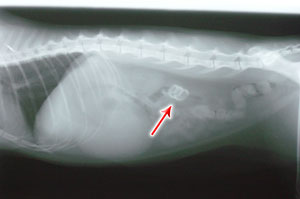

Meanwhile, the man who brought the cat started explaining what had happened to the receptionist. "My cat's name is SCIPIO, and I found him like that when I got home" said the man who introduced himself as Edmund. About an hour passed before Dr. Ghazi came out of the operating room with his usual smile, holding Scipio who was still asleep in a recovery box. "You won't believe this!" muttered Dr Ghazi, "Look what I found in his stomach!" he said while holding a telephone cord in his left hand (see picture). How could this happen? I have never seen such a thing. That's a very persistant cat (must have been hungry too!). Scipio could not eat or drink for 7 days, and he had to be fed intravenousely during that time. Because of his taste for plastic wires, we had to put him a collar to prevent him from eating the intraveinal tube. It took about 10 days for Scipio to return home, only to find that his master Edmund had replaced all the phones with cordless ones.